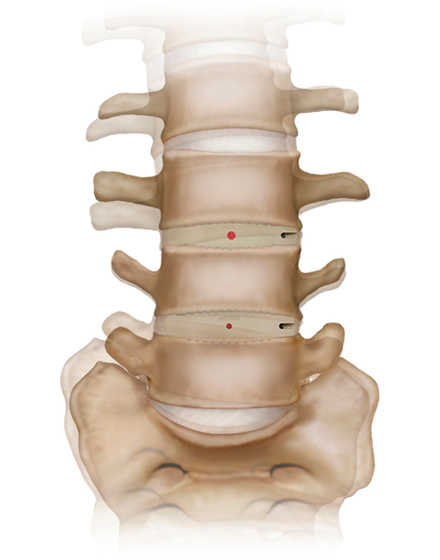

低侵襲脊椎側方固定術 XLIF (エックスリフ)、OLIF(オーリフ)

適応となる疾患:腰椎椎間板ヘルニア、腰部脊柱管狭窄症、腰椎変性すべり症、腰椎変性側弯症など

日本では2013年から承認されている低侵襲な脊椎側方固定術です。この手術は、トレーニングを受けた医師だけが実施できるため、全国でも限られた医療機関でのみ受けられます。当センターの日方医師は資格を有しているため実施可能です。この手術の最大の利点は脊髄神経を直接触らないで神経を圧迫から解除することにあります。側腹部に約5cmの皮膚切開により、下図のように神経機能を電気モニタリングで随時確認し重要な神経を避けながら椎間板内に人工骨を移植します。その後、腰部から固定術を行います。翌日から起立・歩行が許可され、入院期間は通常10~14日程度になります。